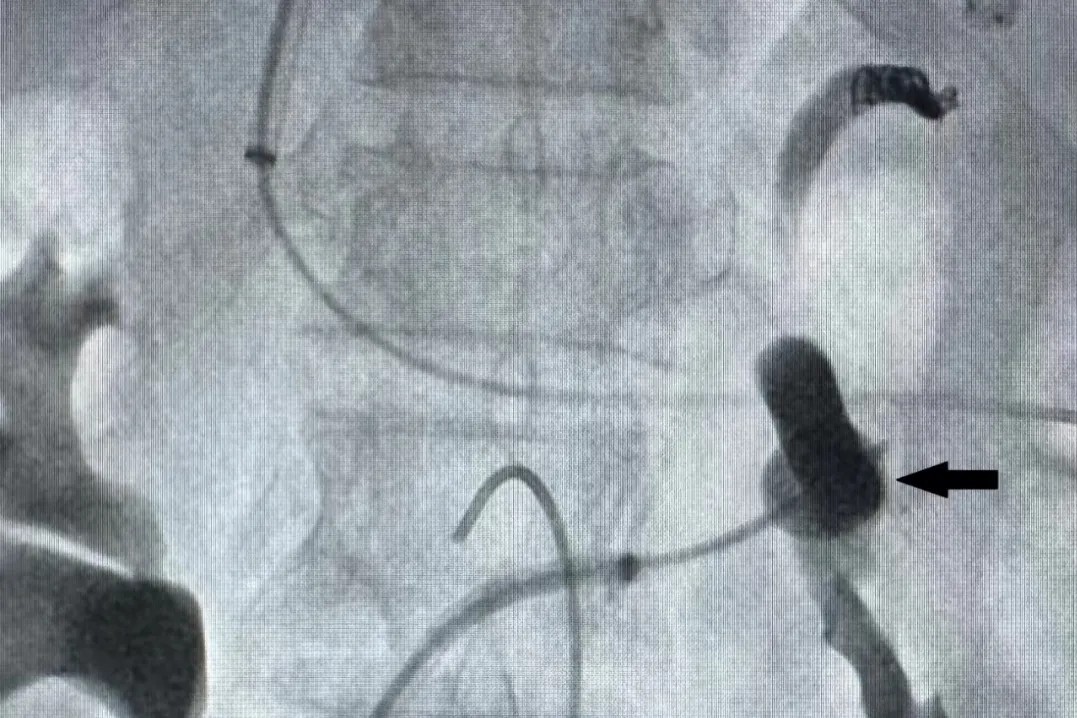

用球囊导管将脾肾分流道堵塞并注入泡沫硬化剂(黑色箭头)